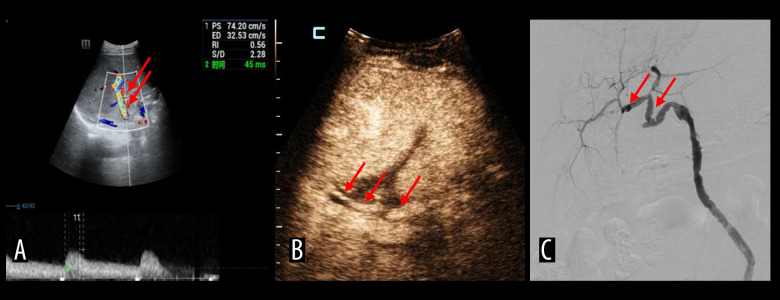

肝动脉血栓形成是肝移植术后最常见、最严重的血管并发症。经导管动脉溶栓具有高选择性、低剂量、局部药物浓度高、对全身凝血功能影响小等优点。动脉内对比增强超声(IA-CEUS)无辐射,可重复,可在床边进行,可作为连续监测的替代方法。我们描述了IA-CEUS在评估连续经导管动脉溶栓治疗肝移植后肝动脉血栓形成的效果中的有效性。材料与方法选取2016年11月至2023年5月肝移植术后诊断为肝动脉血栓形成的患者8例。所有8例患者均采用尿激酶连续经导管动脉溶栓。在溶栓治疗期间,对每位患者进行IA-CEUS动态监测。采用肝动脉数字减影血管造影对结果进行验证。结果2例患者出现肝动脉灌注缺损。6例患者动脉灌注良好。3例患者出现胆囊瘤。一名患者患上了夹层动脉瘤。一名患者出现假性动脉瘤,导管移位。1例患者出现腹膜后血肿。所有患者均未出现造影剂相关并发症。结论IA-CEUS作为评价经导管动脉溶栓治疗肝移植术后肝动脉血栓疗效的新选择是安全可行的。

BACKGROUND Hepatic artery thrombosis is the most common and severe vascular complication after liver transplantations. Transcatheter arterial thrombolysis is a viable alternative with high selectivity, low drug dosage, high local drug concentration, and minimal effect on systemic coagulation function. Intra-arterial contrast-enhanced ultrasound (IA-CEUS) is radiation-free and repeatable, can be performed bedside, and could be an alternative for continuous monitoring. We described the efficacy of IA-CEUS in assessing the effect of continuous transcatheter arterial thrombolysis in post-liver transplant hepatic artery thrombosis in a series of cases. MATERIAL AND METHODS Eight patients with diagnosis of hepatic artery thrombosis after liver transplantation between November 2016 and May 2023 were selected. All 8 patients underwent continuous transcatheter arterial thrombolysis, using urokinase. Dynamic IA-CEUS monitoring was performed for each patient during the thrombolysis treatment. Hepatic artery digital subtraction angiography was used to verify the results. RESULTS Two patients showed a hepatic artery perfusion defect. Six patients demonstrated good perfusion of artery. Three patients developed biloma. One patient developed a dissection aneurysm. One patient developed a pseudoaneurysm with catheter displacement in it. One patient developed retroperitoneal hematoma. None of the patients experienced contrast agent-related complications. CONCLUSIONS IA-CEUS was found to be safe and feasible as a new option for evaluating the efficacy of transcatheter arterial thrombolysis in post-liver transplant hepatic artery thrombosis.